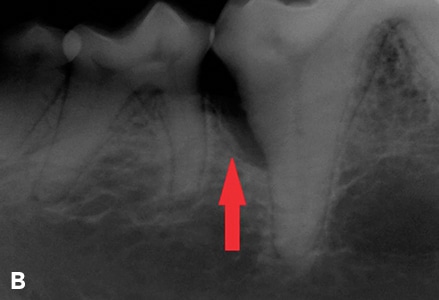

As pet owners, we all want to ensure that our furry companions receive the best possible veterinary care. When it comes to dental health, dental radiographs are a valuable tool that can help prevent complications during extractions. In this blog post, we'll explore the importance of dental radiographs in preventing complications during extractions, and how they can improve your pet's overall dental health.